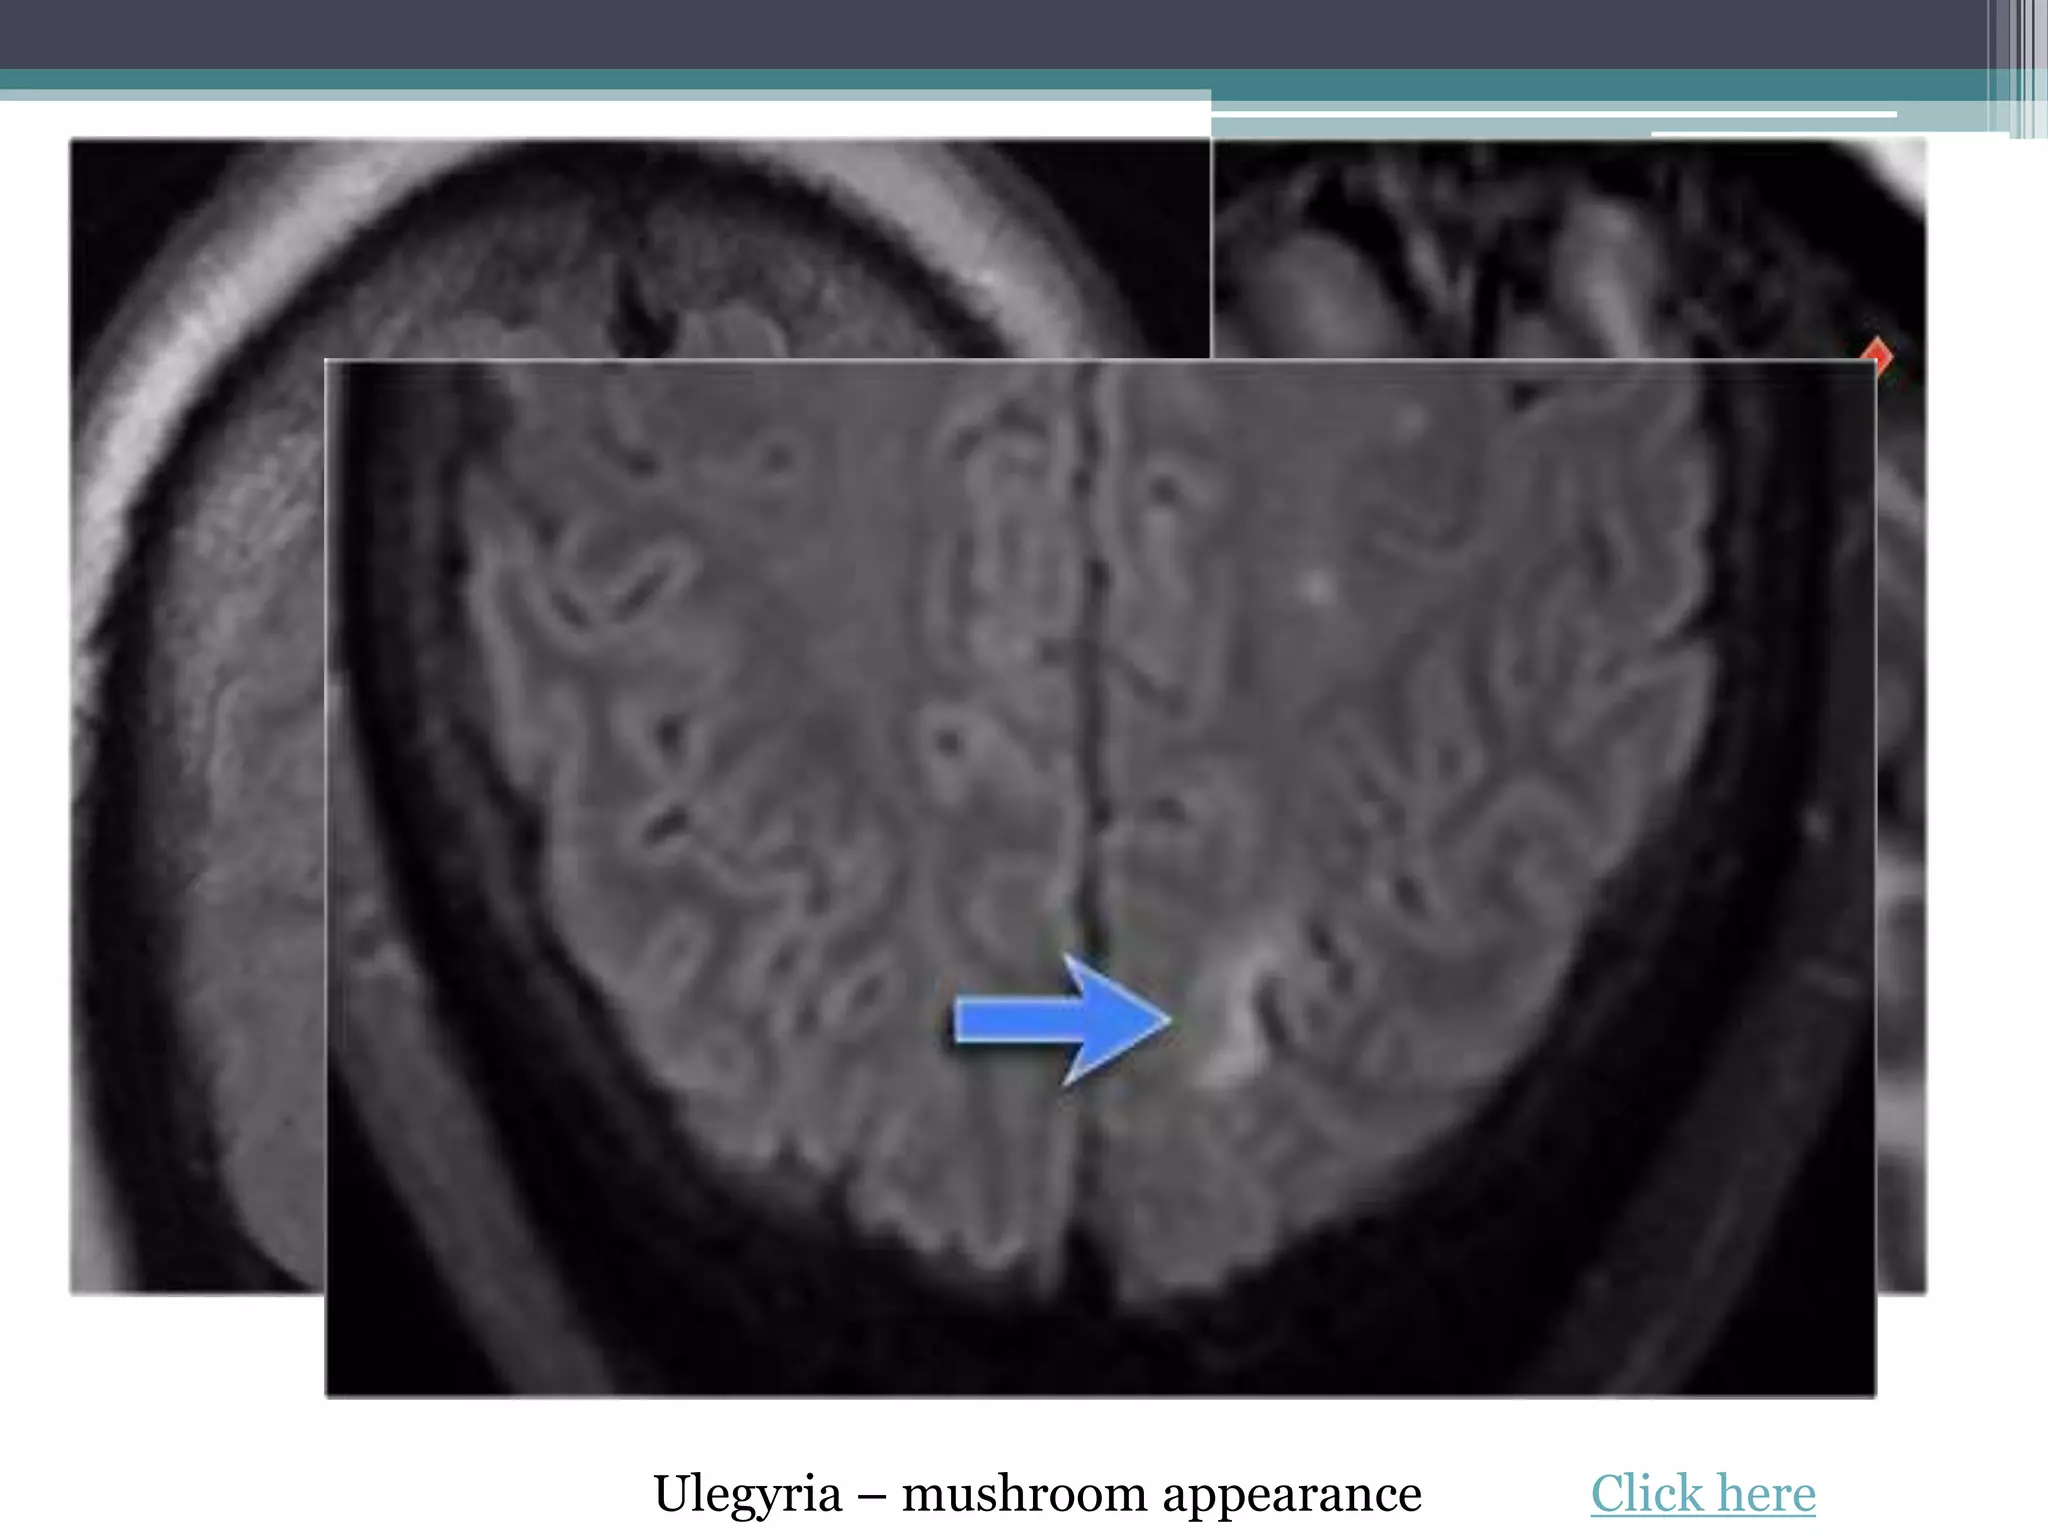

3. Cortical / glial scars - ulegyria • Meningitis or perinatal insult

• Ulegyria – specific type of scar

• Cerebral cortical scarring due to

perinatal ischemia

• Ulegyria – pedunculated gyri –

mushroom appearance click here

Ulegyria – mushroom appearance Click here